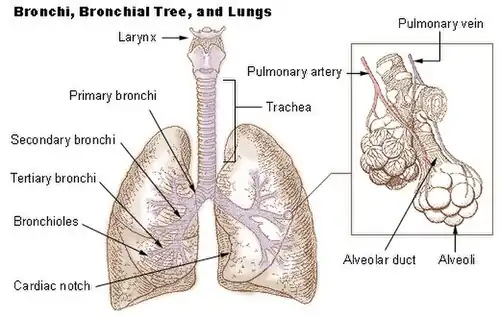

Humans have two lungs, a right lung and a left lung. They are situated within the thoracic cavity of the chest. The right lung is bigger than the left, and the left lung shares space in the chest with the heart. The lungs together weigh approximately 1.3 kilograms (2.9 lb), and the right is heavier. The lungs are part of the lower respiratory tract that begins at the trachea and branches into the bronchi and bronchioles, which receive air breathed in via the conducting zone. These divide until air reaches microscopic alveoli, where gas exchange takes place. Together, the lungs contain approximately 2,400 kilometers (1,500 mi) of airways and 300 to 500 million alveoli. Each lung is enclosed within a pleural sac of two pleurae which allows the inner and outer walls to slide over each other whilst breathing takes place, without much friction. The inner visceral pleura divides each lung as fissures into sections called lobes. The right lung has three lobes and the left has two. The lobes are further divided into bronchopulmonary segments and lobules. The lungs have a unique blood supply, receiving deoxygenated blood sent from the heart to receive oxygen (the pulmonary circulation) and a separate supply of oxygenated blood (the bronchial circulation).

Segments

The primary bronchi enter the lungs at the hilum and initially branch into secondary bronchi also known as lobar bronchi that supply air to each lobe of the lung. The lobar bronchi branch into tertiary bronchi also known as segmental bronchi and these supply air to the further divisions of the lobes known as bronchopulmonary segments. Each bronchopulmonary segment has its own (segmental) bronchus and arterial supply.[8] Segments for the left and right lung are shown in the table.[5] The segmental anatomy is useful clinically for localising disease processes in the lungs.[5] A segment is a discrete unit that can be surgically removed without seriously affecting surrounding tissue.[9]

Bronchial airways

In the bronchi there are incomplete tracheal rings of cartilage and smaller plates of cartilage that keep them open.[25]: 472 Bronchioles are too narrow to support cartilage and their walls are of smooth muscle, and this is largely absent in the narrower respiratory bronchioles which are mainly just of epithelium.[25]: 472 The absence of cartilage in the terminal bronchioles gives them an alternative name of membranous bronchioles.[26]

Respiratory zone

The conducting zone of the respiratory tract ends at the terminal bronchioles when they branch into the respiratory bronchioles. This marks the beginning of the terminal respiratory unit called the acinus which includes the respiratory bronchioles, the alveolar ducts, alveolar sacs, and alveoli.[27] An acinus measures up to 10 mm in diameter.[28] A primary pulmonary lobule is the part of the lung distal to the respiratory bronchiole.[29] Thus, it includes the alveolar ducts, sacs, and alveoli but not the respiratory bronchioles.[30]

The unit described as the secondary pulmonary lobule is the lobule most referred to as the pulmonary lobule or respiratory lobule.[25]: 489 [31] This lobule is a discrete unit that is the smallest component of the lung that can be seen without aid.[29] The secondary pulmonary lobule is likely to be made up of between 30 and 50 primary lobules.[30] The lobule is supplied by a terminal bronchiole that branches into respiratory bronchioles. The respiratory bronchioles supply the alveoli in each acinus and is accompanied by a pulmonary artery branch. Each lobule is enclosed by an interlobular septum. Each acinus is incompletely separated by an intralobular septum.[28]

The respiratory bronchiole gives rise to the alveolar ducts that lead to the alveolar sacs, which contain two or more alveoli.[20] The walls of the alveoli are extremely thin allowing a fast rate of diffusion. The alveoli have interconnecting small air passages in their walls known as the pores of Kohn.[20]

Respiratory tract

The lower respiratory tract is part of the respiratory system, and consists of the trachea and the structures below this including the lungs.[32] The trachea receives air from the pharynx and travels down to a place where it splits (the carina) into a right and left primary bronchus. These supply air to the right and left lungs, splitting progressively into the secondary and tertiary bronchi for the lobes of the lungs, and into smaller and smaller bronchioles until they become the respiratory bronchioles. These in turn supply air through alveolar ducts into the alveoli, where the exchange of gases take place.[32] Oxygen breathed in, diffuses through the walls of the alveoli into the enveloping capillaries and into the circulation,[20] and carbon dioxide diffuses from the blood into the lungs to be breathed out.